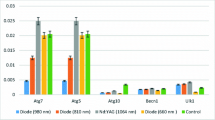

The results of mean TGF-β, PDGF, and bFGF expressions after laser irradiations with different wavelengths are showed in Fig. 1.

The one-way ANOVA test indicated that expression values of the growth factors, PDGF and bFGF, were significantly affected by irradiation of different wavelength types of lasers (p < 0.001); however, expression value of the TGF-β was not affected by irradiation of different wavelength types of lasers (p > 0.05) (Table 2).

When the PDGF values were evaluated, there were statistically significant differences among Nd:YAG laser- and 660-nm laser-irradiated groups and control group (p < 0.05); however, there were no statistically significant differences among Nd:YAG laser-, 980-nm laser-, and 810-nm laser-irradiated groups (p > 0.05).

When bFGF values were evaluated, there were statistically significant differences between 980-nm laser-irradiated group and control group and 660-nm laser-irradiated group (p < 0.05) and also between Nd:YAG laser-irradiated group and control group (p < 0.05); however, there were no statistically significant differences among other groups (p > 0.05) (Table 3).